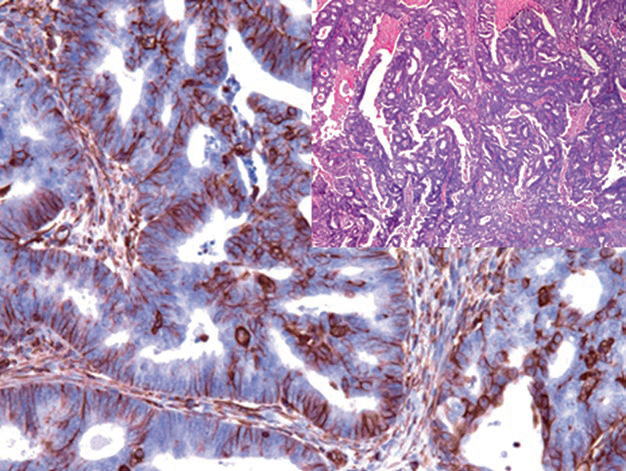

图片

图1. 子宫内膜样癌中,肿瘤性腺体强阳性表达Vimentin。